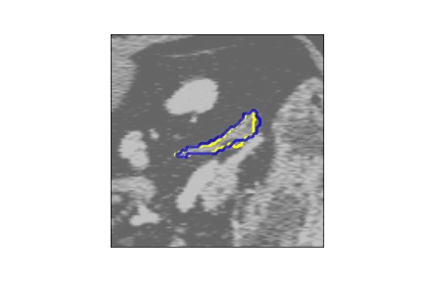

The human annotations are imperfect, especially when produced by junior practitioners. Multi-expert consensus is usually regarded as golden standard, while this annotation protocol is too expensive to implement in many real-world projects. In this study, we propose a method to refine human annotation, named Neural Annotation Refinement (NeAR). It is based on a learnable implicit function, which decodes a latent vector into represented shape. By integrating the appearance as an input of implicit functions, the appearance-aware NeAR fixes the annotation artefacts. Our method is demonstrated on the application of adrenal gland analysis. We first show that the NeAR can repair distorted golden standards on a public adrenal gland segmentation dataset. Besides, we develop a new Adrenal gLand ANalysis (ALAN) dataset with the proposed NeAR, where each case consists of a 3D shape of adrenal gland and its diagnosis label (normal vs. abnormal) assigned by experts. We show that models trained on the shapes repaired by the NeAR can diagnose adrenal glands better than the original ones. The ALAN dataset will be open-source, with 1,594 shapes for adrenal gland diagnosis, which serves as a new benchmark for medical shape analysis. Code and dataset are available at https://github.com/M3DV/NeAR.